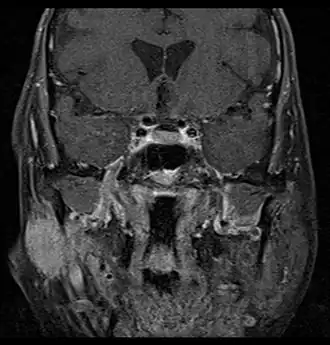

Pleomorphic adenomaCoronal MRI showing right parotid adenoid cystic carcinoma.